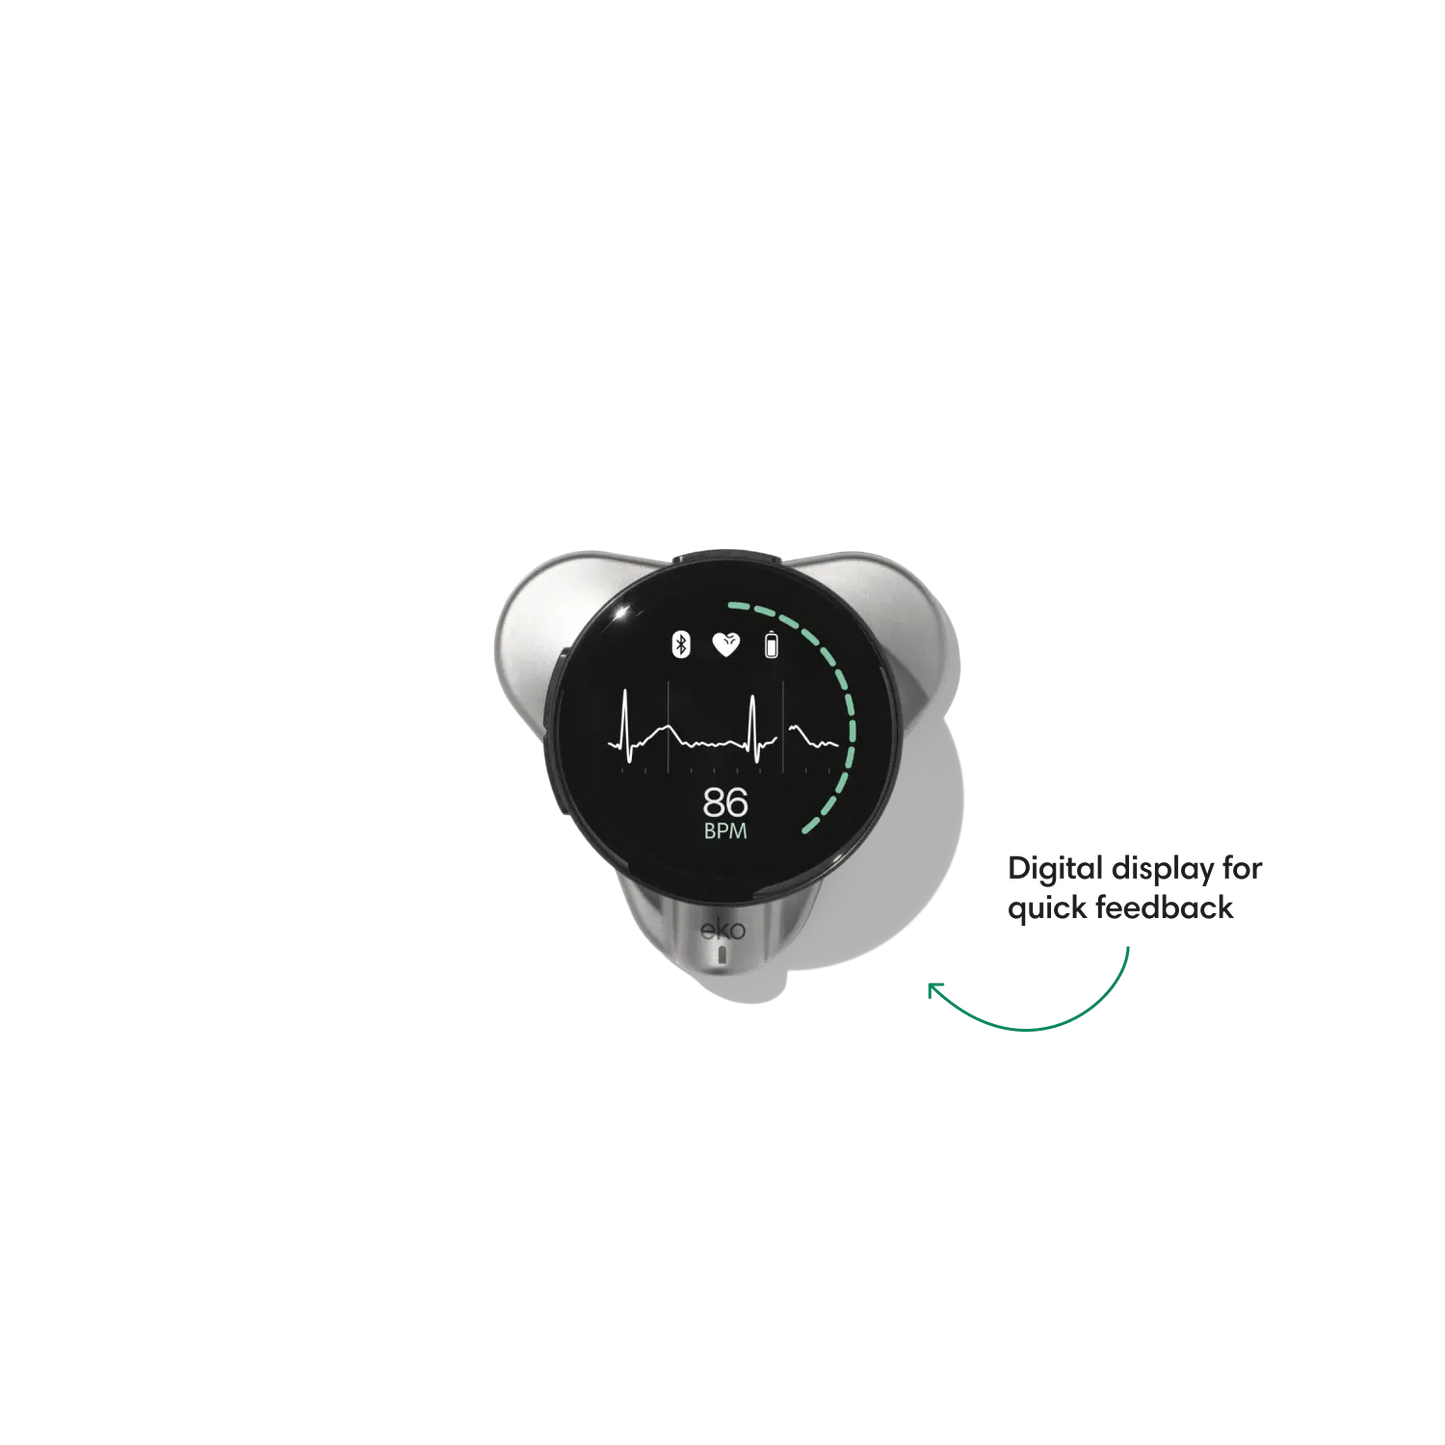

Go beyond sound alone.

For the first time ever, measure heart rate, visualize 3-lead ECG, and see detection results — right on a built-in, full-color display.